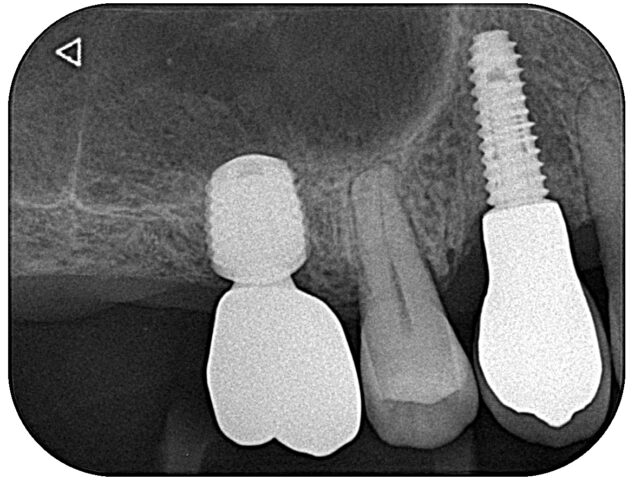

| 通院時の年齢 | 60代 |

|---|---|

| 性別 | 女性 |

| 通院回数 | 3ヶ月 |

| 通院目的 | 入れ歯が嫌なのでインプラントにしたい |

| 処置内容 | 右下65 左下46にインプラント |

| 費用 | 約170万円 |

| 備考 | 昔治療済の歯をそのままに入れ歯の部位のみ治療希望され、十分満足された。 |